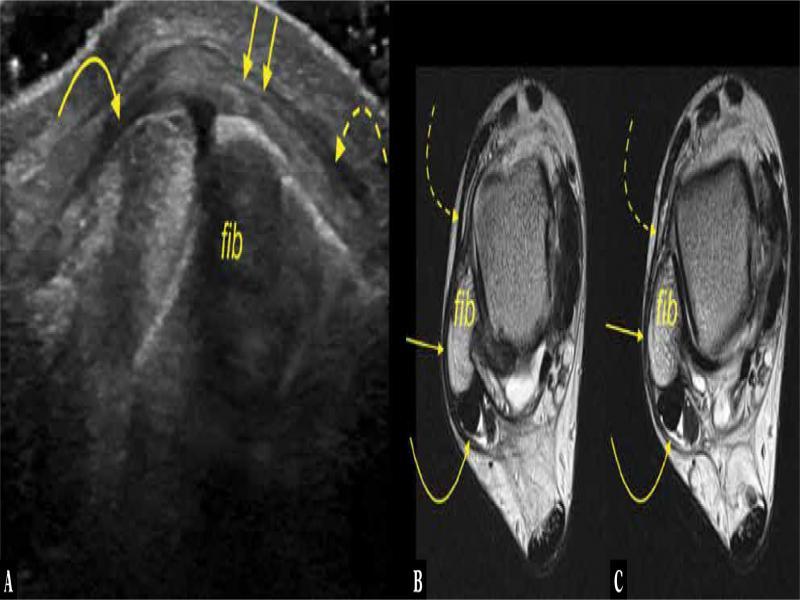

Fig. 5.

A 52-year-old patient presented with retromalleolar pain. A, B, C. transverse section on ultrasound. D. proton density-weighted transverse section. The interconnection (arrows) between the SPR (letter R) and IER (curved arrow) and ATFL. Fib – fibula

The IER served as an intermediate station for connecting the SPR to the ATFL in 8 cases on MRI (12.7%) and in 5 cases on US (7.9%), but the difference was not significant (p >0.05) (Fig. 3). In those cases, a direct connection between the SPR and the ATFL was also noted (n = 13, 20.6%) (Fig. 5).